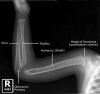

- Humerus AP/Lateral view

- Humerus Ossification Centers